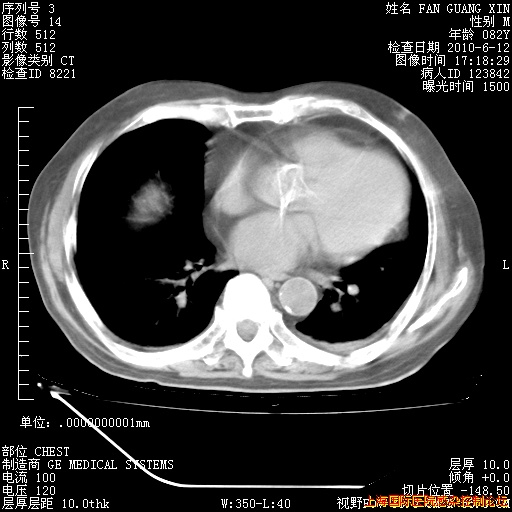

今天复查CT

今天CT

整整相隔30天的肺部CT好像有所好转啊。甲强龙减量第3天,需要观察体温。